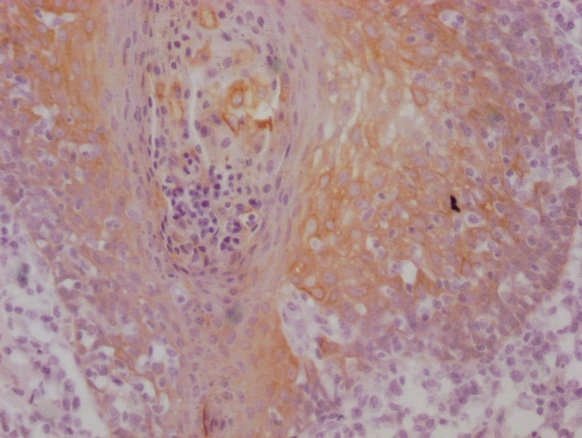

IHC image of MACO0502 diluted at 1:100 and staining in paraffin-embedded human tonsil tissue performed on a Leica BondTM system. After dewaxing and hydration, antigen retrieval was mediated by high pressure in a citrate buffer (pH 6.0). Section was blocked with 10% normal goat serum 30min at RT. Then primary antibody (1% BSA) was incubated at 4°C overnight. The primary is detected by a Goat anti-mouse IgG polymer labeled by HRP and visualized using 0.05% DAB.